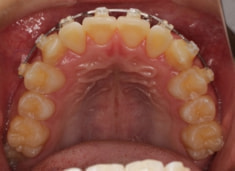

小児期ケース:反対咬合+上顎両側3番埋伏歯

(受け口+3番目の永久歯が左右両方とも埋まってしまい、はえてこない)

治療法:上顎急速拡大装置+クリアスナップ+フェイスマスク+上顎3番は開窓牽引CT写真にて位置確認

治療前